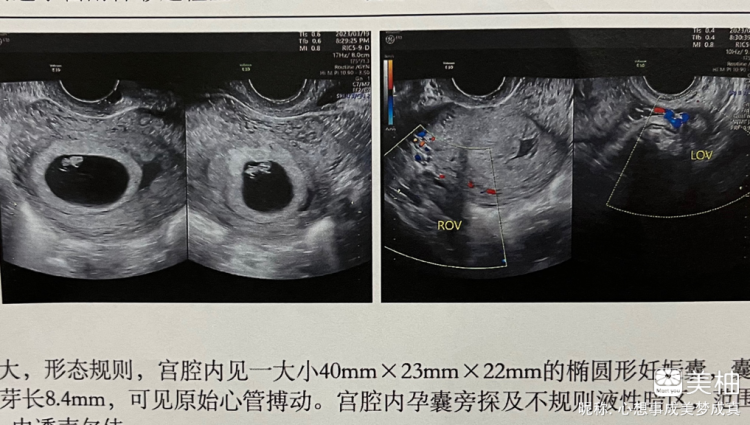

在临床实践中,孕囊大小是评估妊娠状态的重要指标医生通过超声测量孕囊的三个径线长宽高,结合头臀长CRL等数据,可判断胚胎发育是否符合孕周是否存在流产风险或滋养细胞疾病等异常情况若孕囊直径与孕周不符如过小可能提示胚胎停育,过大可能关联葡萄胎,需进一步排查原因并干预我。